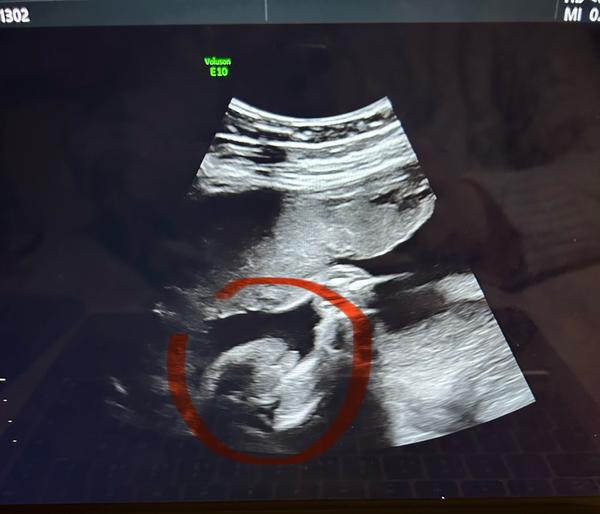

doktor mi stále nepotvrdil pohlaví. I já na jedné fotce vidím holku, na druhé kluka. Co myslíte? :D

@lenca554 já bych spíš řekla holka. Ale nejsem odborník, jen máma dvou holek 🙂 takže bych počkala na potvrzení od dr.